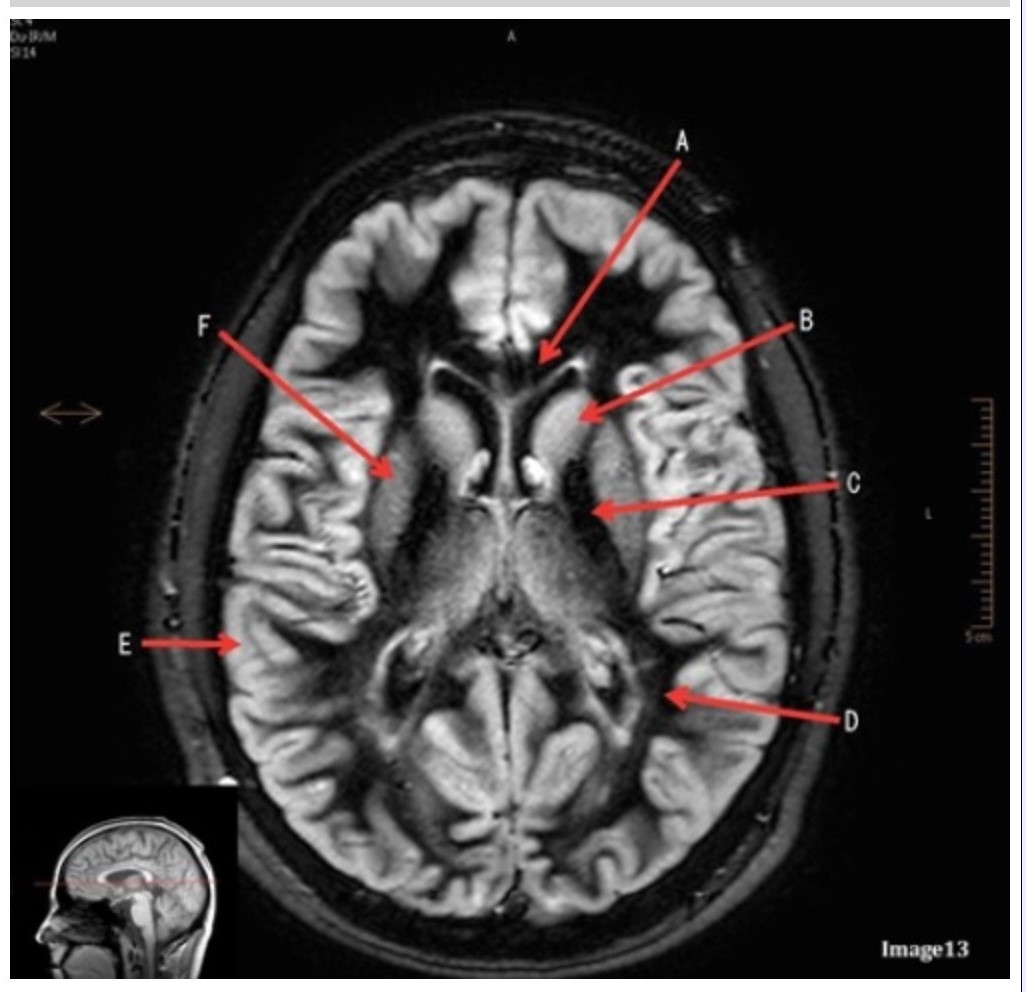

Letter B in Image 13 is pointing to:

A. Splenium of the corpus callosum

B. Genu of the corpus callosum

C. Lentiform nucleus

D. Caudate nucleus

E. Internal capsule

Letter F in Image 13 is pointing to:

A. Grey matter

B. White matter

C. Lentiform nucleus

D. Caudate nucleus

E. Internal capsule

Letter D in Image 13 is pointing to:

A. Grey matter

B. White matter

C. Lentiform nucleus

D. Caudate nucleus

E. Internal capsule

Letter C in Image 13 is pointing to:

A. Splenium of the corpus callosum

B. Genu of the corpus callosum

C. Lentiform nucleus

D. Caudate nucleus

E. Internal capsule

Letter E in Image 13 is pointing to:

A. Grey matter

B. White matter

C. Lentiform nucleus

D. Caudate nucleus

E. Internal capsule

Image 9 is an example of a _____ weighted sequence acquired in the _______ scan plane.

A. T1; Axial

B. T2 FLAIR; Sagittal

C. T2; Axial

D. T2; Coronal